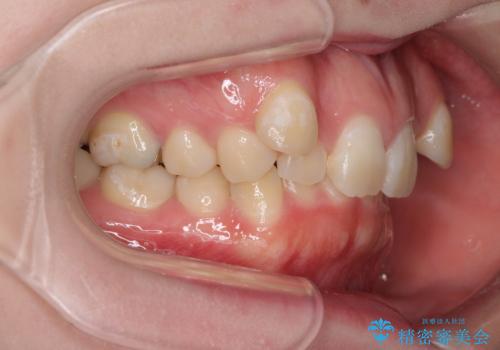

著しい八重歯を短期間で改善 ワイヤー装置による抜歯矯正

- 八重歯と下顎小臼歯の欠損を気にして来院された患者様です。

下顎小臼歯の欠損により過蓋咬合となっていたため、下顎は臼歯を起こすことで咬み合わせを改善し、八重歯は第一小臼歯2本を抜歯し、補助装置を使用して速やかに改善することとしました。

著しい過蓋咬合の改善が必要であった割には、治療期間は2年強と標準的でした。

八重歯は3,4か月で速やかに改善されました。